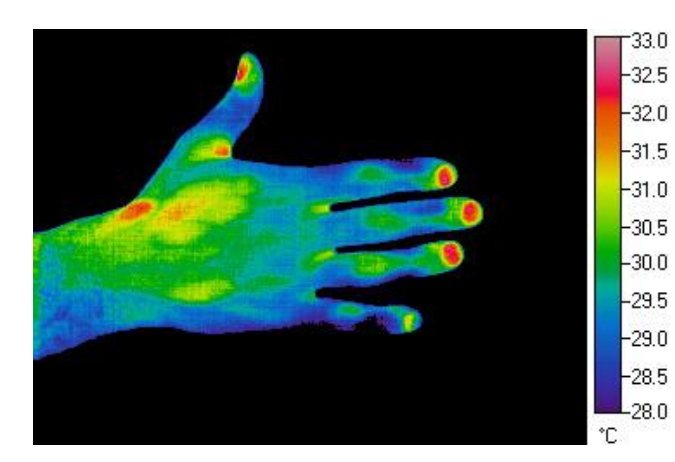

Infra Red Sensors (IR camera) (2)

Temperature measurement at a distance

Colour-scale coded temperature map